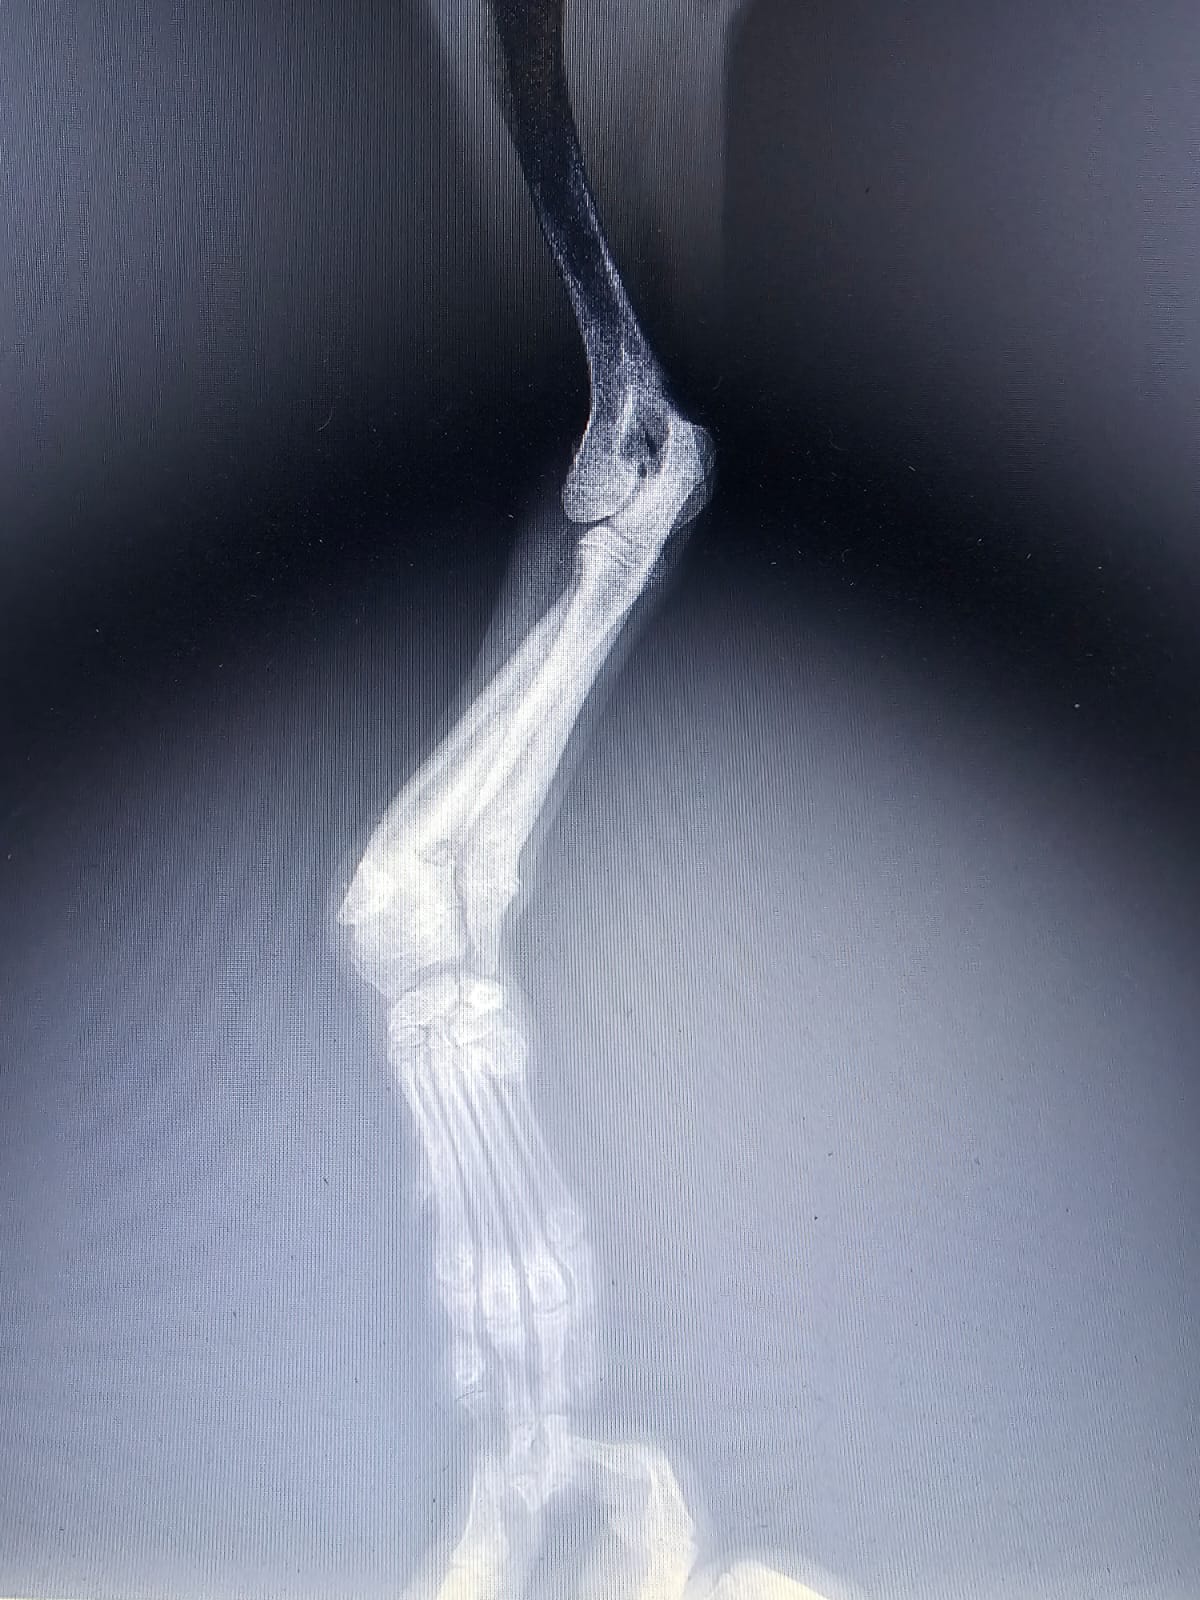

Gatlin was hit by a car . He had a broken front leg. Rescued from Saida. Very sweet, calm friendly. Good with other dogs. DOB: 2/2/2025